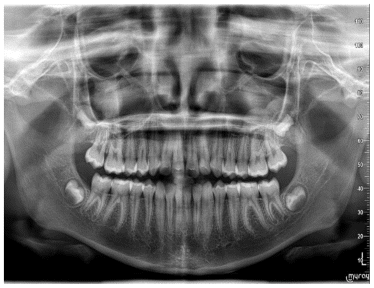

Case 2

The patient was a growing female child who presented during early mixed dentition with an anterior crossbite associated with a deep overbite and a marked sagittal discrepancy (Figures 12–19). The initial clinical examination revealed a negative overjet, complete anterior deep bite, and a functional Class III occlusal pattern. Extraoral assessment showed a flattened facial profile, while cephalometric analysis confirmed a skeletal imbalance characterized by increased SNA and SNB values, an ANB of 0°, negative Withs appraisal, and significant dentoalveolar compensations, including proclination of both upper and lower incisors (Table 3). The vertical pattern was predominantly hypodivergent, suggesting a high risk of unfavorable mandibular growth progression if left untreated. Given the patient’s young age and growth potential, an early interceptive treatment was planned to use the AMCOP® TC appliance, with the aim of correcting the anterior crossbite, improving neuromuscular balance, and guiding sagittal and vertical development during growth. The appliance was worn nightly and for additional daytime hours, according to patient compliance.

After 18 months of treatment, a clear clinical improvement was observed. Intraoral examination demonstrated complete correction of the anterior crossbite, with establishment of a positive overjet and normalization of the anterior occlusal relationship. The deep bite was reduced, allowing more functional anterior guidance. Occlusal relationships improved toward a stable dental Class I, and the need for excessive dentoalveolar compensation was reduced. Cephalometric reassessment showed an overall improvement in sagittal relationships and incisor inclinations, with a trend toward normalization of the previously altered parameters. These findings indicate that early functional therapy with the AMCOP® TC appliance was effective in intercepting the developing Class III malocclusion, improving occlusal function, and potentially reducing the severity of future skeletal discrepancies (Table 4).